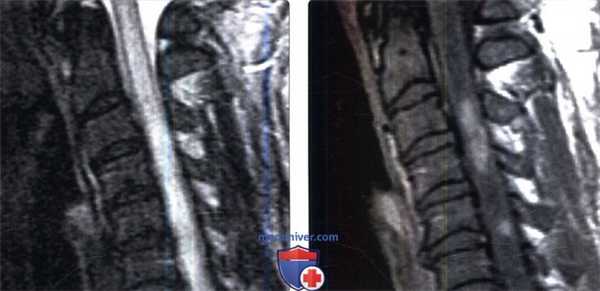

(Слева) Сагиттальный срез, FS Т2-ВИ, пациент после курса лучевой терапии по поводу рака полости рта: патологическое веретеновидное утолщение и гиперинтенсивность сигнала шейного отдела спинного мозга на уровне С2-СЗ. Обратите также внимание на диффузное подавление сигнала костного мозга тел позвонков вследствие его постлучевой жировой перестройки.

(Справа) Сагиттальный срез, FS T1-ВИ с КУ, пациент после курса лучевой терапии по поводу рака полости рта: в толще спинного мозга на уровне С2 определяется очаг накопления контраста. Обратите внимание на диффузное подавление сигнала костного мозга тел позвонков вследствие его постлучевой жировой перестройки.